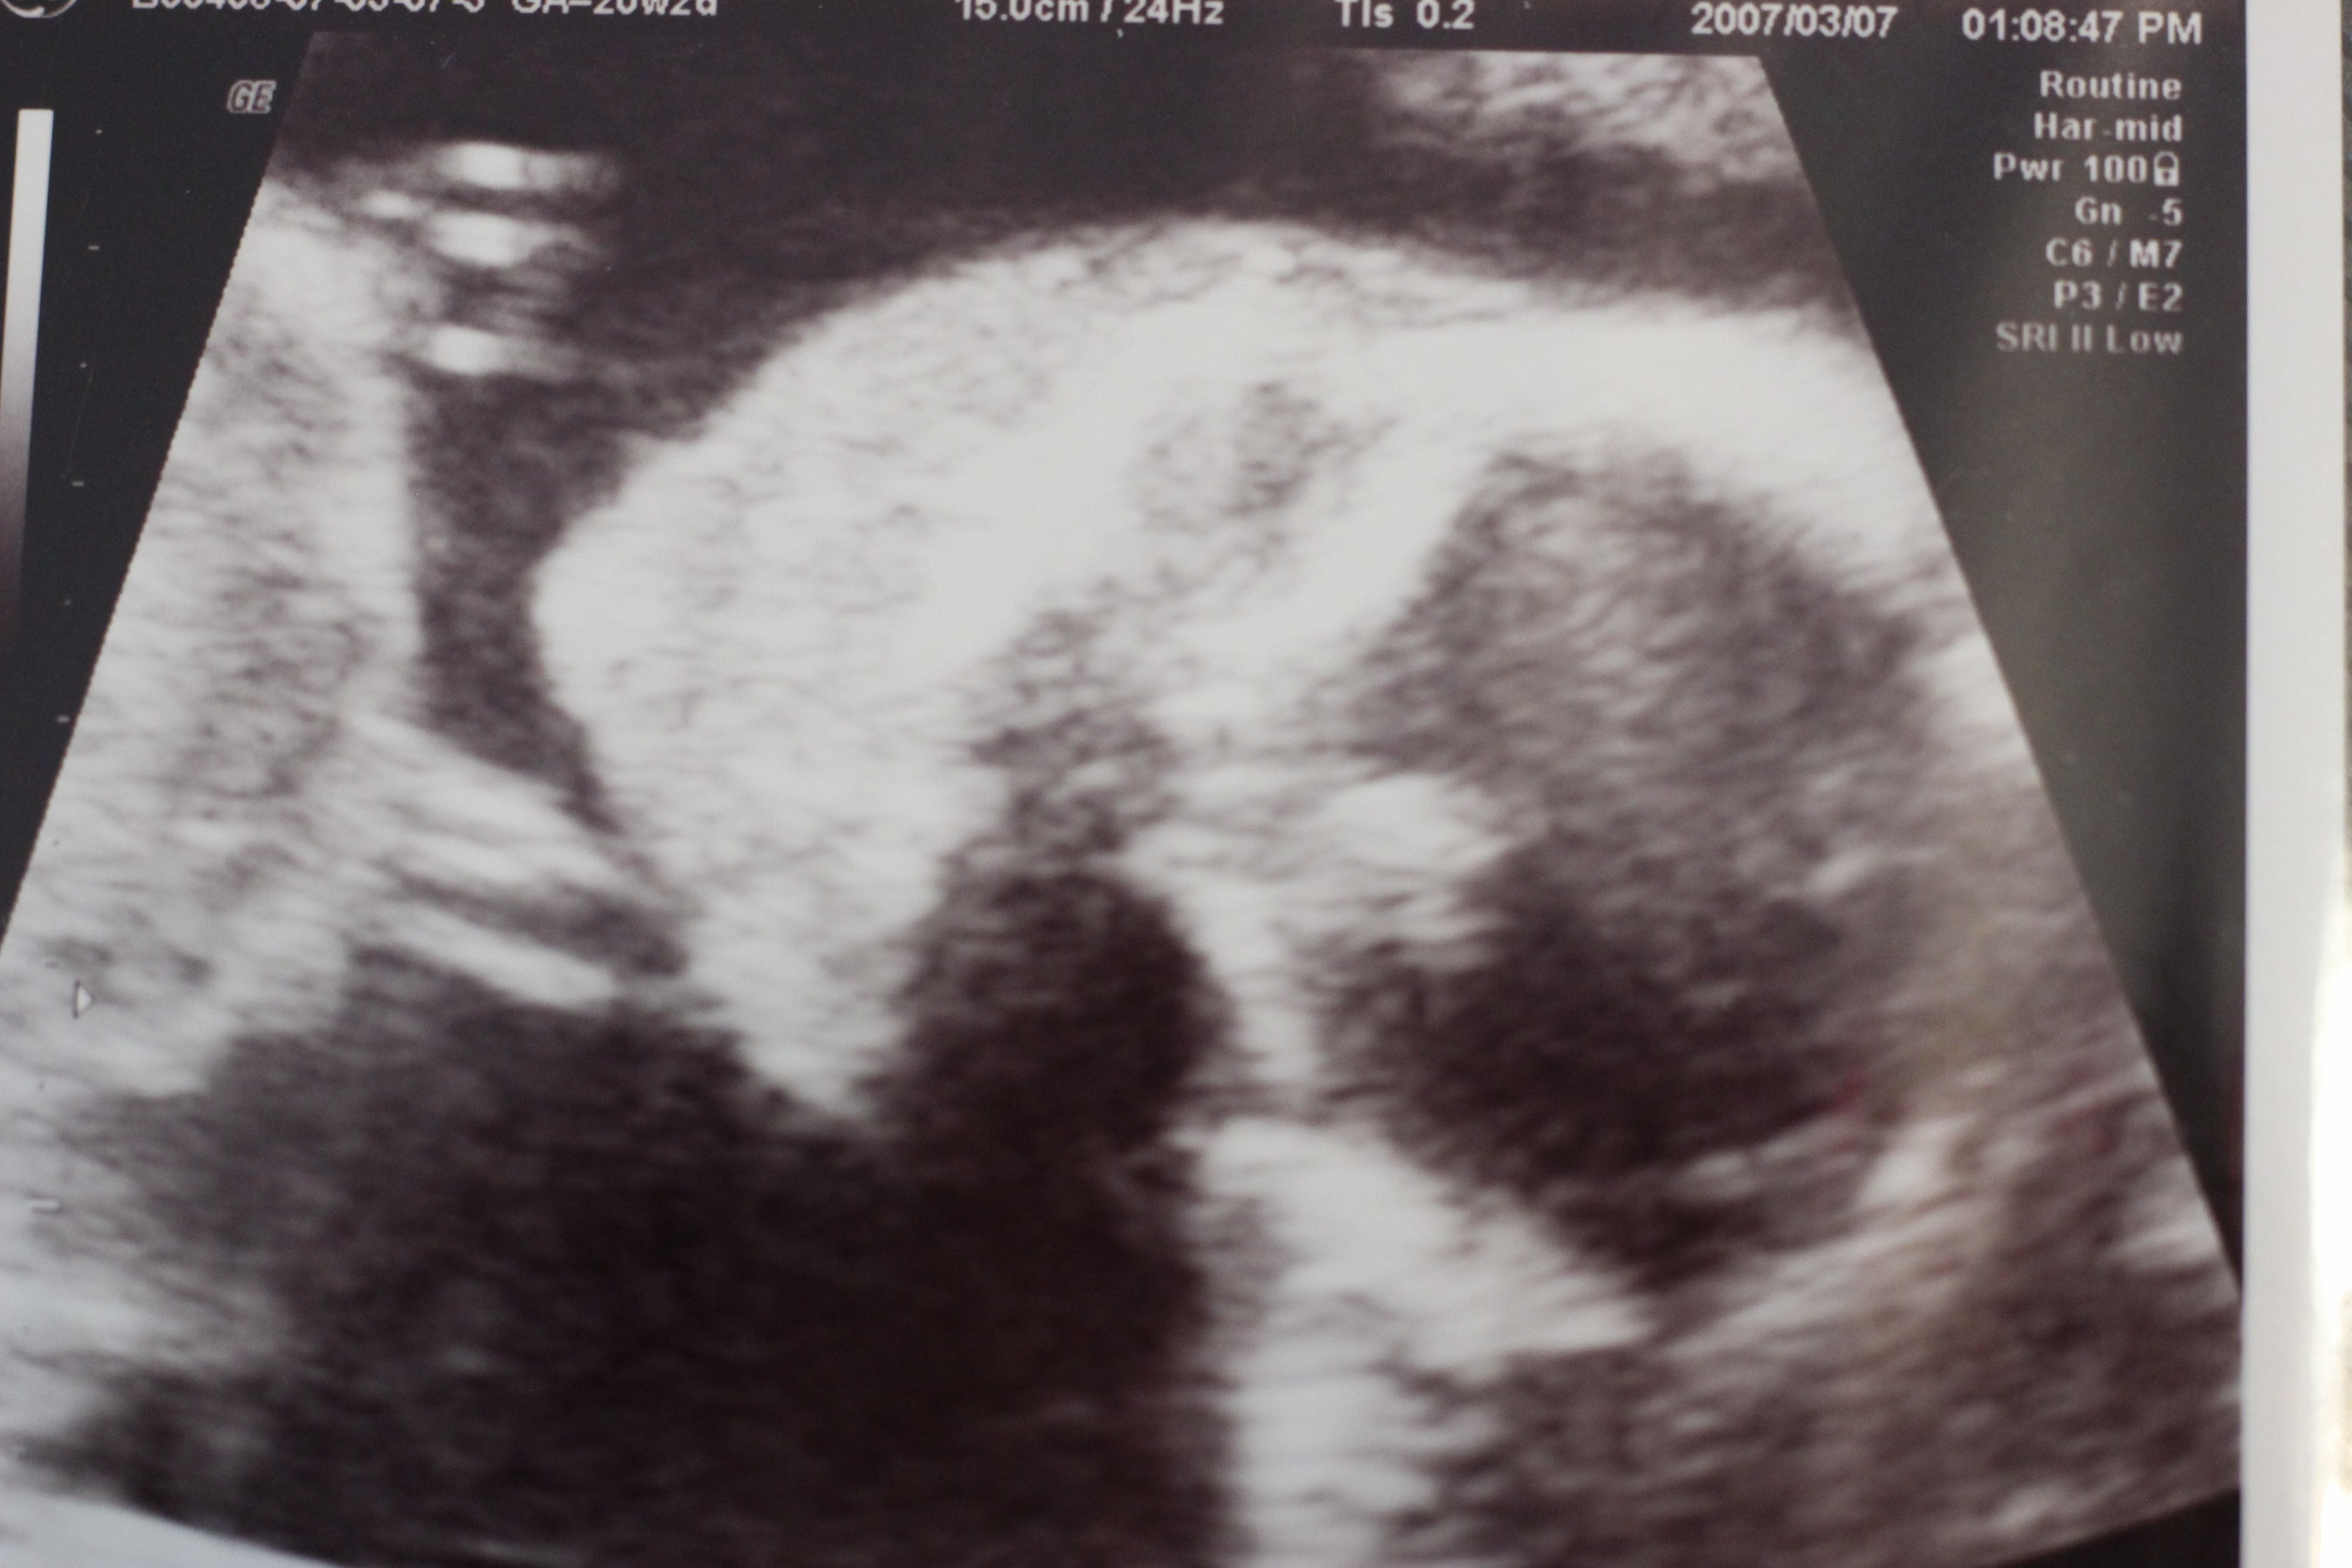

妊娠20週目のエコー写真

妊娠20週目の2D画像。横になった姿勢で、顔のアップの左側に写っている顎の細さが分かりました。赤ちゃんの推定体重345g。私の腹囲は人生初の90cm台になり、どこからみても貫禄充分なお母さんでした。

妊娠20週目の3D画像。早くも引っ込み思案な性格の表れか、エコー写真を撮ろうとすると胎盤の裏に隠れようとしています。何度も撮り直してようやく撮れたのがこちら。この頃、保健センターで催される母親学級で、産院が同じプレママと出会いました。